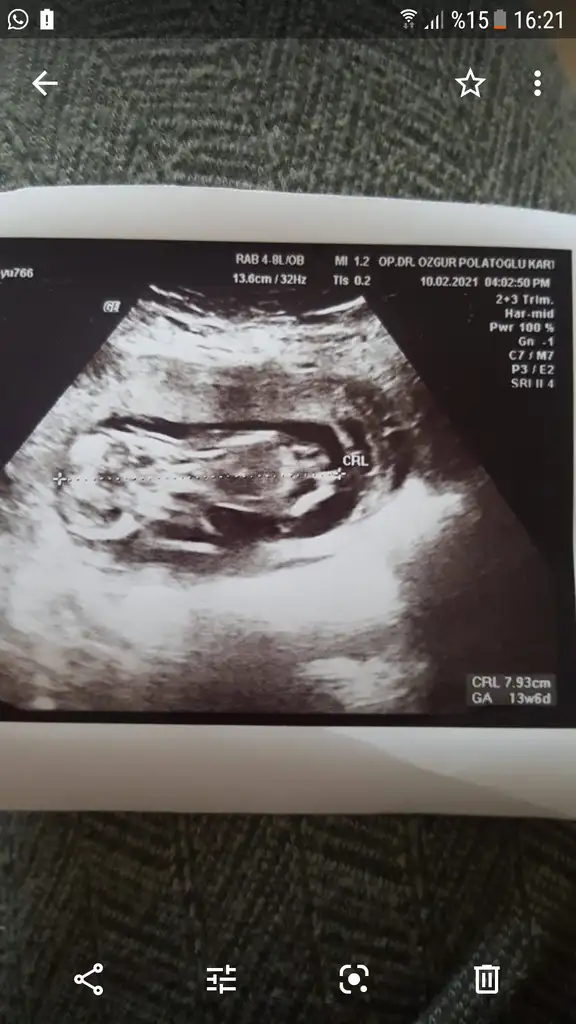

Ya başka ultrason yok ama 9+5 bir ultrasonum var. Doktor şimdilik erkek gibi dedi ama bilmiyorumNet değil USG başka USG varsa paylaşın sanki kız gibi amin olamadım![]()

Emin olamadım zaten belki erkektir olursa USG paylaşınYa başka ultrason yok ama 9+5 bir ultrasonum var. Doktor şimdilik erkek gibi dedi ama bilmiyorum![]()

Kız dedi doktor 16. Haftada erkek diye düşünüyordum ama olmadı11 hafta göre erkek görünüyor![]()